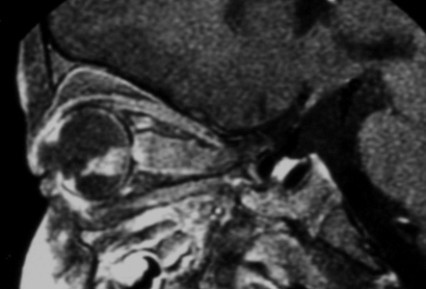

전통적인 초음파 B-스캔은 종양 내 석회화를 감지할 수 있으며, 고주파 초음파 B-스캔은 기존 초음파보다 더 높은 해상도를 제공하고 종양과 눈 앞부분의 근접성을 확인할 수 있다. 자기 공명 영상(MRI)은 시신경 침범, 맥락막 침범, 공막 침범, 두개내 침범과 같은 고위험 특징을 감지할 수 있다. 전산화 단층 촬영(CT)은 방사선이 RB1 유전자 돌연변이 환자에게서 더 많은 눈 종양의 형성을 자극할 수 있으므로 일반적으로 피한다.[37]

안저 소견, CT, MRI, 초음파 진단 등으로 확진한다.